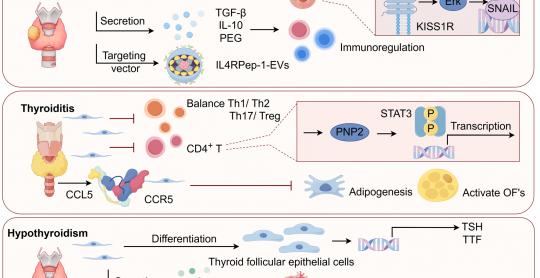

Journal of Endocrinology & Metabolism

Vol. 15, No. 4, Oct 2025 pages 119-129

By Yan Fen Liu et al.